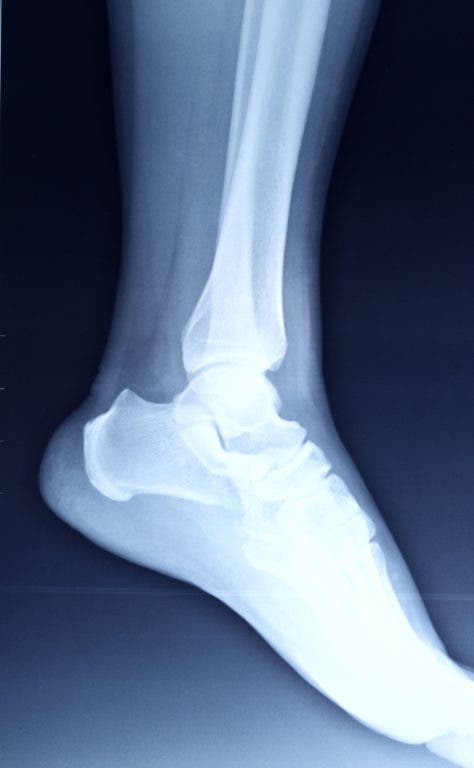

How do you know how strong your bones are? There’s a test for that. A bone mineral density (BMD) test diagnoses osteoporosis and determines your risk for future fracture. Early diagnosis is important because osteoporosis can develop undetected for decades until a fracture occurs.

With a doctor’s referral, bone density testing is available at the Arthritis and Osteoporosis Center at Mills Health Center in San Mateo. It takes less than 20 minutes to perform the exam. Don’t wait for a fracture to occur. Step on it!